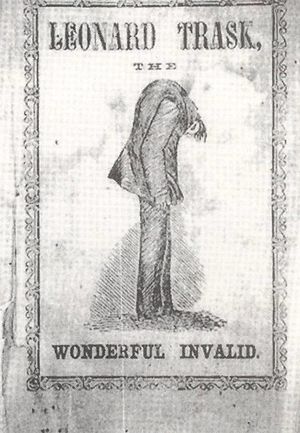

- Leonard Trask,[25] born in 1805 and who condition provided the first American description of ankylosing spondylitis.

- ^ Jayson MI (مارس 2003). "Leonard Trask: the wonderful invalid: the first American description of ankylosing spondylitis". Rheumatology (journal). British Society for Rheumatology. 48 (3): 612–613. PMID 12632411. Retrieved 18 ديسمبر 2011.